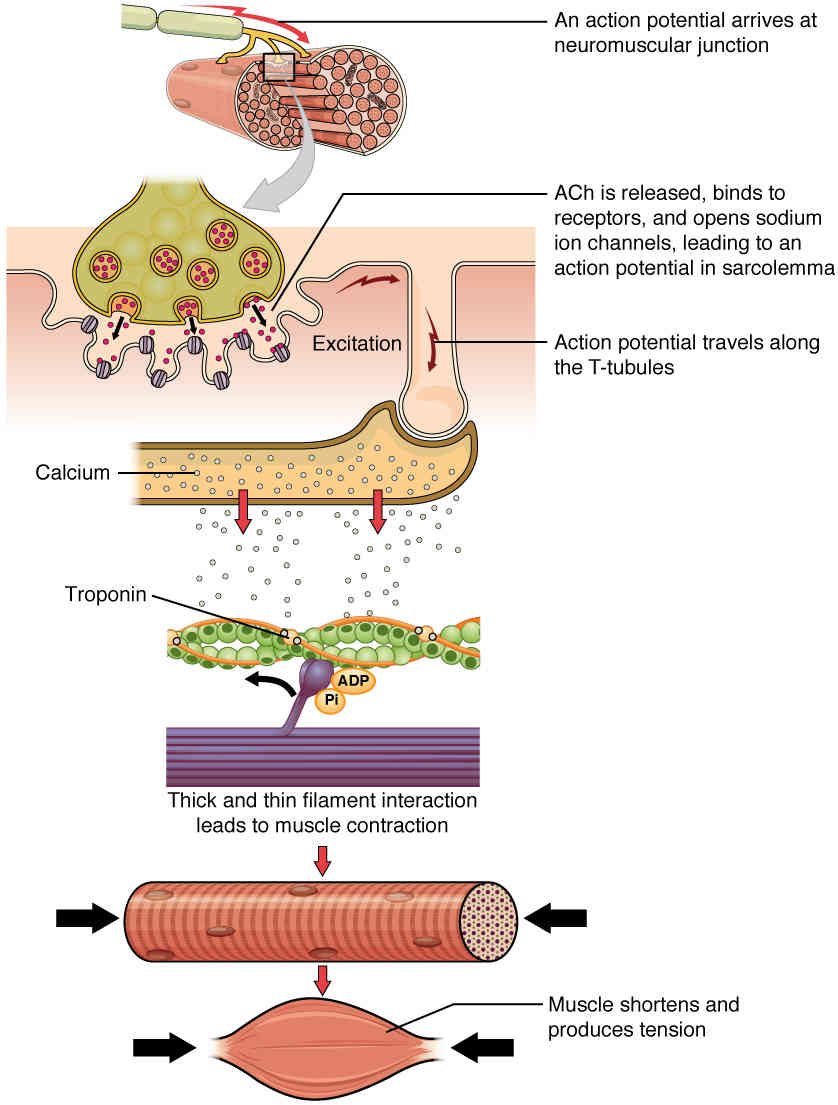

This page is under construction. For now, it is just a resource of the images found in the OpenStax Anatomy and Physiology Handbook. It wil slowly change into a revision tool. Each slide has a number. Use this to refer to the slide. When completed, it will have an unlabelled section, with labelled slides in parallel. On the unlabelled slides, write your answer and use the labelled slide to assess yourself. Keep track by also noting the number on each slide. Improvement at each attempt is important, more so than full marks on a first attempt.